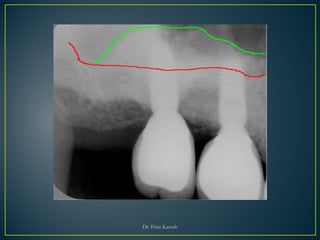

• Maxilla is 35 times more edentulous than

mandible

• Maxillary sinus continues pneumatization

throughout life.

• The available bone is lost from the inferior

expansion of the sinus after tooth loss,

involving the residual ridge region